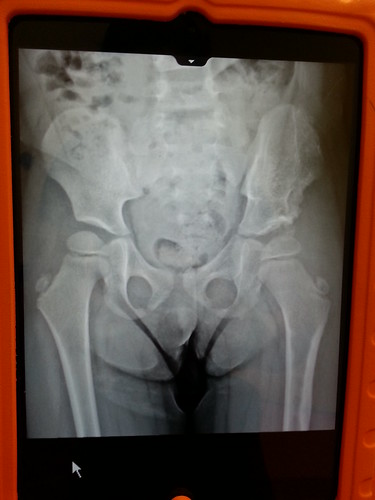

On the morning of May 9th our friend Danielle and her daughter Sophie came over for a play date and to chat about adoption. It was a nice visit and fun play time for the girls. After lunch and they left, we headed to Texas Scottish Rite Hospital for Dani’s yearly hip check. We started with height/weight and an xray.

Dani cooperated with Dr. Podezwa and he said that she is doing great. Everything looked good and we are clear for another year. WOO HOO!!